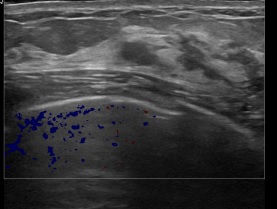

아산유외과개원후 863번째 유방암진단

상기환자는 양성추정결절 추적관찰위해 내원하신 50대 중반

여성분으로 의심스러운 좌측유방혹 조직검사 시행해 유방암 진단되었습니다.